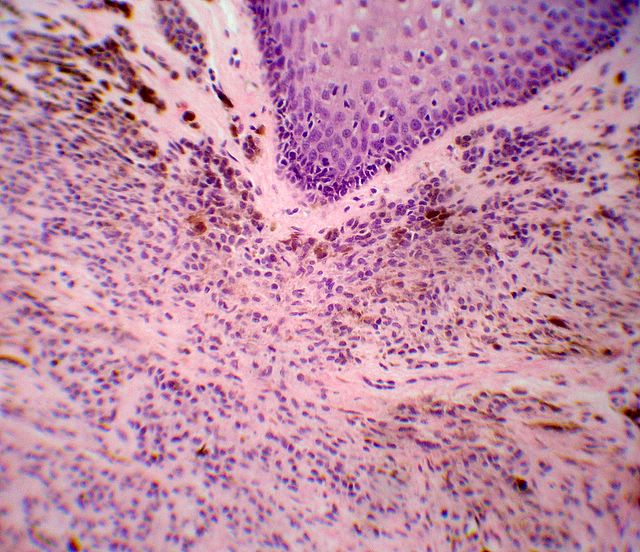

Descripcion histologica

Diagnostico